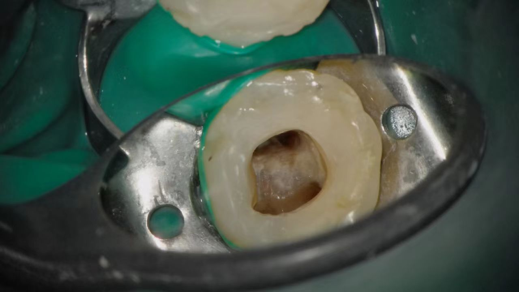

4K超清图像效果

企业微信截图_17496941442680.png

智能曝光

通过系统的智能曝光算法,在显微镜不同的光照环境,以及不同的手术器械介入,对画面曝光智能调整,让医生不再受到图像过曝的困扰。

企业微信截图_17496941466927.png

真实色彩

4K分辨率下,支持BT.2020广色域,专业的色彩调整,确保色差△C00<3,让医生所见即所得。